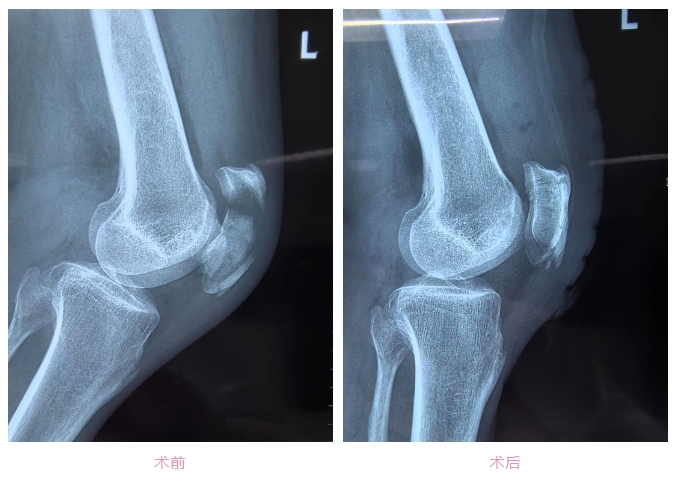

2月3日,大年初四,60岁的陈大爷在家中摔倒,导致了左髌骨粉碎性骨折。通过X光显示,当时,陈大爷不仅左髌骨粉碎性骨折,且碎成了4块。经景德镇市第一人民医院骨科医师团队诊断,打石膏等保守治疗已经无法达到满意的治疗效果,于是市一院骨科专家袁志峰建议陈大爷通过手术的方式纠正并防止再次移位。

然而,钛针固定术使用的是不可吸收的金属材料,需二次手术取出内固定,不仅存在二次手术风险,还会给患者带来额外的痛苦和经济负担。而且,陈大爷对于“二次手术”心理上十分畏惧。 考虑到陈大爷及其家属的意愿,市一院骨科团队袁志峰主任和邓皓医师再三研究探讨,寻求最佳治疗方式,最终决定为陈大爷实施髌骨切开全线固定术。该手术采用可吸收、高强度缝线结合特殊捆扎的方法来固定骨折块,无需二次手术。 “全线固定就如同用网袋固定破碎的髌骨,防止移位,对于手术的精密性要求较高。”邓皓分析,虽然全线固定避免了二次手术的风险,但此类手术更适合劳动负担小、活动量小的老年人,对于术后康复时间更长。而钛针固定法则更加稳固,更加适合年轻人,两种手术各有利弊。 2月8日上午,手术由市一院骨科袁志峰主任医师和邓皓操刀,十分成功。手术历时50分钟。术后第3天,陈大爷便能拄着拐杖下床活动。 “无论是钛针固定或是全线固定,作为医生,我们就要综合考虑到患者的心理、生理以及经济、家庭等各方面的情况,帮助患者去选择更加适合、有效的治疗方式,这才是‘医者仁心’”。骨科主任袁志峰表示。